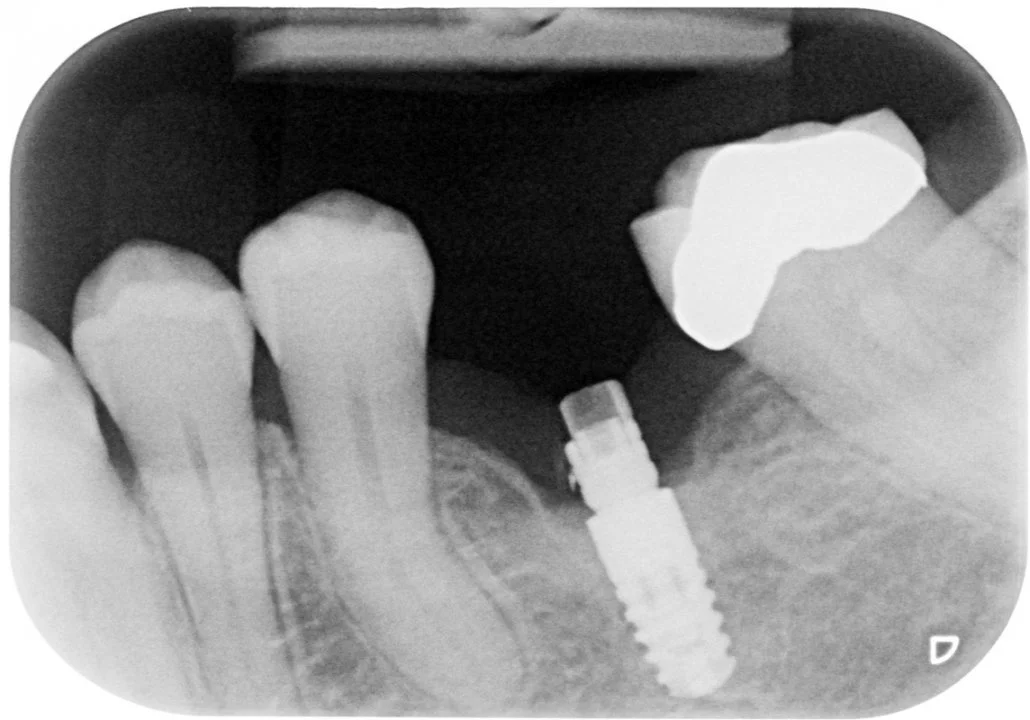

Exploding Abutments

We have seen some major issues recently with the use of ‘fake’ abutments on implants we have placed. One such case is seen here where the referring dentist did not use Ceramic Designs and sadly this has harmed everyone involved.